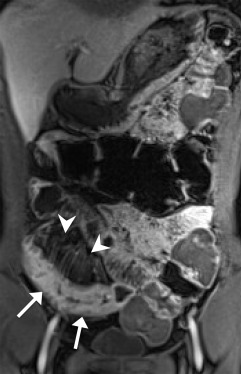

Enlarged mesenteric lymph nodes were most clearly seen on the postcontrast VIBE images, presenting as ovoid or lobulated nodular lesions between the mesenteric vessels (Figure 1 ). Engorged vasa recta were often identified adjacent to an active inflamed intestinal loop and were also best demonstrated on the postcontrast VIBE images (Figure 2 ). Fibrofatty proliferation was best seen on the coronal T2-weighted half-Fourier single-shot turbo spin-echo (T2-HASTE) images that presented as increased mesenteric fat surrounding the affected intestinal loops (Figure 3 ). Fistula tracts were often identified between an inflamed bowel and adjacent structures, showing tethering of the two structures with a contrast-enhanced fistula tract between them (Figure 4 ). Meanwhile, abscesses often manifested as fluid collections with a high signal on T2-HASTE images and well-enhanced walls on the postcontrast VIBE images (Figure 5 ).

A 40-year-old woman. Coronal T2-HASTE image shows skipped disease-involved ileal ...

Figure 3.

A 40-year-old woman. Coronal T2-HASTE image shows skipped disease-involved ileal segments with abnormal wall-thickening (arrows). There is increased amount of the adjacent mesenteric fat (arrowheads), indicating fibrofatty proliferation. T2-HASTE = T2-weighted half-Fourier single-shot turbo spin-echo.

No definite inflammatory spondyloarthropathy (such as sacroiliitis) was identified in this study. Interestingly, avascular necrosis of the femoral head was identified in two patients, despite the lack of clinical symptoms. One of the patients had imaging with MR enterography four times during this study period for monitoring the treatment response. Avascular necrosis was identified since the third MR enterography session, which showed serpiginous lines over the superior portion of the bilateral femoral heads (Figure 6 ). This might relate to her long-term steroid usage for treatment of repeated flare-ups.

The same patient as in Figure 3. Coronal T2-HASTE image shows hypointense ...

Figure 6.

The same patient as in Figure 3 . Coronal T2-HASTE image shows hypointense irregular serpiginous lines over the superior portion of bilateral femoral heads (arrows). The femoral heads are preserved without collapse, suggesting Stage II avascular necrosis. T2-HASTE = T2-weighted half-Fourier single-shot turbo spin-echo.